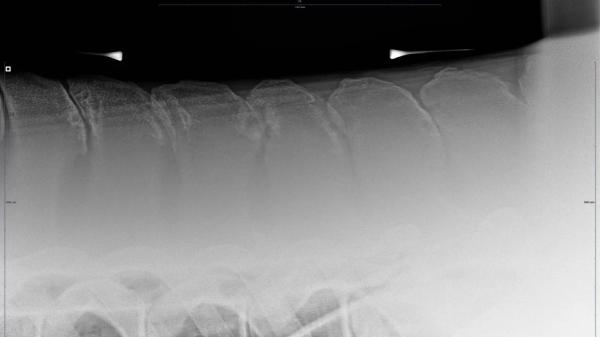

Fjordhästen Skogheims Tinder ska vara den första fjordhästen någonsin som placerat sig i Breeders Open bland de stora bruna hästarna. Bara några månader tidigare höll Kine Storbæk på att förlora honom efter kastrationen.